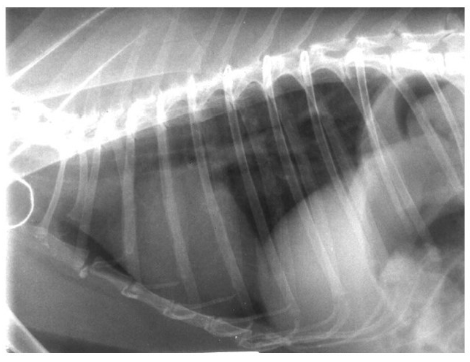

What species is this radiograph from and what is important to recognise about it?

rabbit

it’s large compared to thoracic space, sits vertically against sternum and is very cranial - anatomical location in relation to techniques we may perform